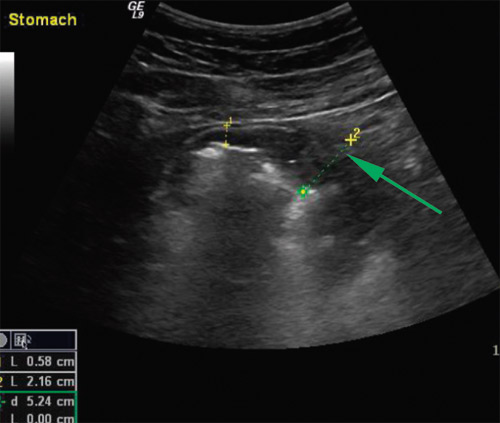

Det ble utført en gastroenterologisk ultralydundersøkelse. Denne viste små mengder ascites og lett forstørret milt. Det mest påfallende funnet var imidlertid betydelig fortykket og foldet ventrikkelslimhinne, målt tykkelse var opp mot 2 cm (fig 1).

Pasienten fikk intravenøs behandling med ganciklovir i 14 dager, så overgang til peroral valaciklovir i fem uker. I tillegg fikk han albumin intravenøst – 40 g/dag – i en uke. Han fikk også diuretika for å mobilisere væske. Som følge av dette regimet gikk ødemene raskt tilbake og vekten ble normalisert. 14 dager etter oppstart av antiviral behandling ble det utført endoskopisk ultralydundersøkelse av ventrikkelen (fig 3a). Det var fortsatt forandringer, men man fikk inntrykk av tilbakegang. Ultralydbildet viste betydelig foldet og fortykket slimhinne, men tykkelsen ble nå målt til ca. 10 mm. Kapselendoskopi viste injiserte slimhinner i ventrikkelen, for øvrig var det normale funn i tynntarmen.

Ny transabdominal og endoskopisk ultralydundersøkelse og endoskopi ble utført etter omtrent tre måneder. Denne viste tilnærmet normalisering av ventrikkelslimhinnen (fig 3b). Ut fra serologisk undersøkelse på cytomegalovirus fant man at det var skjedd en serokonvertering, med fall i IgM og stigning i spesifikt IgG. På dette stadium var pasienten frisk og alle blodprøver normale.

Hyperplastiske ventrikkelslimhinner påvist ved endoskopi er et uspesifikt funn. Endoskopisk er det vanskelig å skille klassisk Ménétriers sykdom fra andre tilstander som gir liknende bilde. Transabdominal og endoskopisk ultralyd gir ofte en god fremstilling av slimhinnen i ventrikkelen og er et nyttig supplement (10).